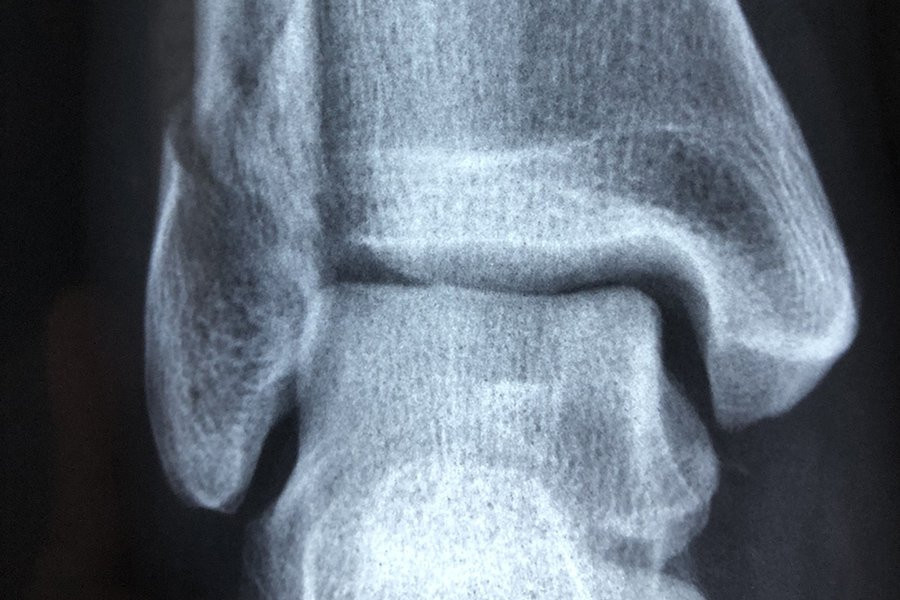

Фото из открытых источников

Форма коленной чашечки человека может быть индикатором того, подвержен ли он большему риску развития остеоартрита, согласно новому исследованию Австралийского национального университета (ANU). Исследование было опубликовано в журнале Osteoarthritis and Cartilage.

Используя передовые методы анализа изображений для создания 3D-моделей сотен костей коленной чашечки, команда затем применила методы моделирования формы для визуализации и измерения формы поверхностей коленной чашечки в трех измерениях.

Хотя они не нашли уникальных особенностей среди коленных чашечек женщин по сравнению с мужчинами, они обнаружили изменения в поверхностях коленной чашечки, которые были более выражены у людей с остеоартритом.

«Удивительно то, что различные суставные поверхности коленной чашечки по-разному меняют форму при остеоартрите и по мере увеличения тяжести заболевания», — сказала Уилсон.